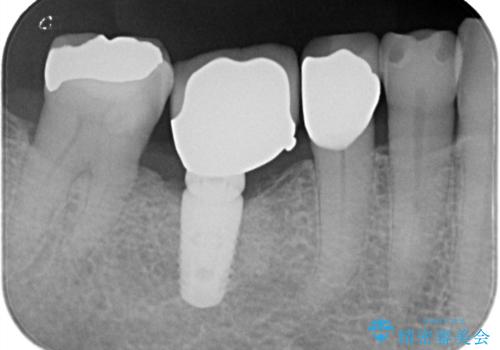

- 虫歯が原因で歯が欠けていました。昔詰めた保険の材料(CR)が劣化しその下が虫歯になっている状態でした。

色々な箇所にCR(保険の材料)を詰めてあったので、CRと虫歯を全部除去した後、オールセラミッククラウンで治療を行いました。

古いCR(保険治療で使用されるプラスチック)を除去すると残りの歯質が薄いため、破折抵抗を考慮しオールセラミッククラウンで治療を行いました。